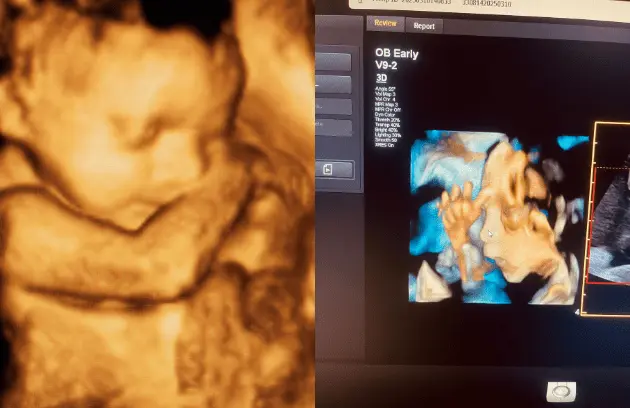

🔹 3D / 4D Ultrasound

3D/4D Ultrasound provides a clear and real-time view of your baby inside the womb. While 3D shows detailed images, 4D allows you to see live movements like smiling or yawning. It enhances bonding between parents and baby while also helping doctors assess physical development. Experience advanced 4D ultrasound in Kathmandu for a memorable and informative pregnancy journey.